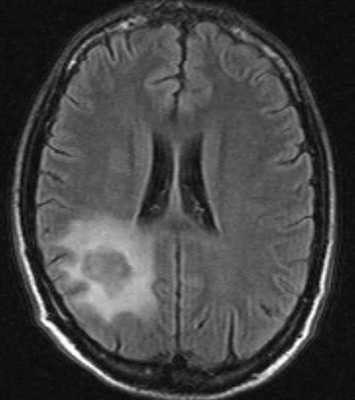

Инфекции быстро прогрессируют, особенно токсоплазмоз. При МРТ виден выраженный отек вокруг очага. Контрастируется при МРТ токсоплазмоз обычно по кольцевому типу.

МРТ головного мозга. Т2-взвешенная аксиальная МРТ. Токсоплазмоз.

Лимфома также контрастируется на МРТ по кольцевому типу, но гипоинтенсивна на Т2-взвешенных МРТ головного мозга. По локализации лимфома чаще располагается перивентрикулярно, в то время как очаги токсоплазмоза в области базальных ганглиев и сопровождаются значительным отеком.